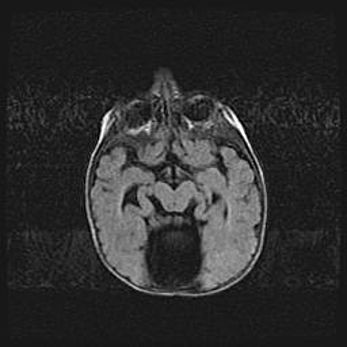

Церебральная ишемия II.

Возраст: 5 дней

Вес: 3400 г

Пол: женский

Окружность головы: 35 см

Срок гестации: 39 недель

Церебральная ишемия – это заболевание, характеризующееся недостаточностью (гипоксией) либо полным прекращением (аноксией) снабжения мозга кислородом по причине закупорки одного или нескольких сосудов. Это приводит к  что метаболическим расстройствам различной степени тяжести в тканях головного мозга, развитию коагуляционных некрозов и гибели нейронов.